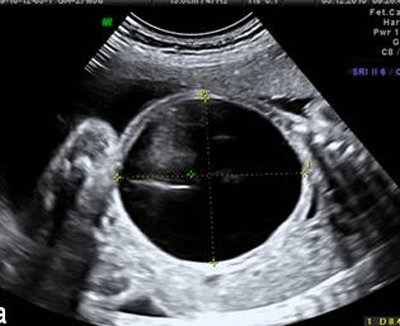

A 26-year-old pregnant woman was referred to our prenatal center for a fetal abdominal cystic mass with severe oligohydramnios detected at 27th week of gestation. Prenatal scan showed a single male fetus with a cystic avascular mass (74×84 mm) located in the left hemi abdomen pushing left hemi diaphragm (Fig. 1).

Figure 1: A huge cyst in fetus compressing surrounding structures |